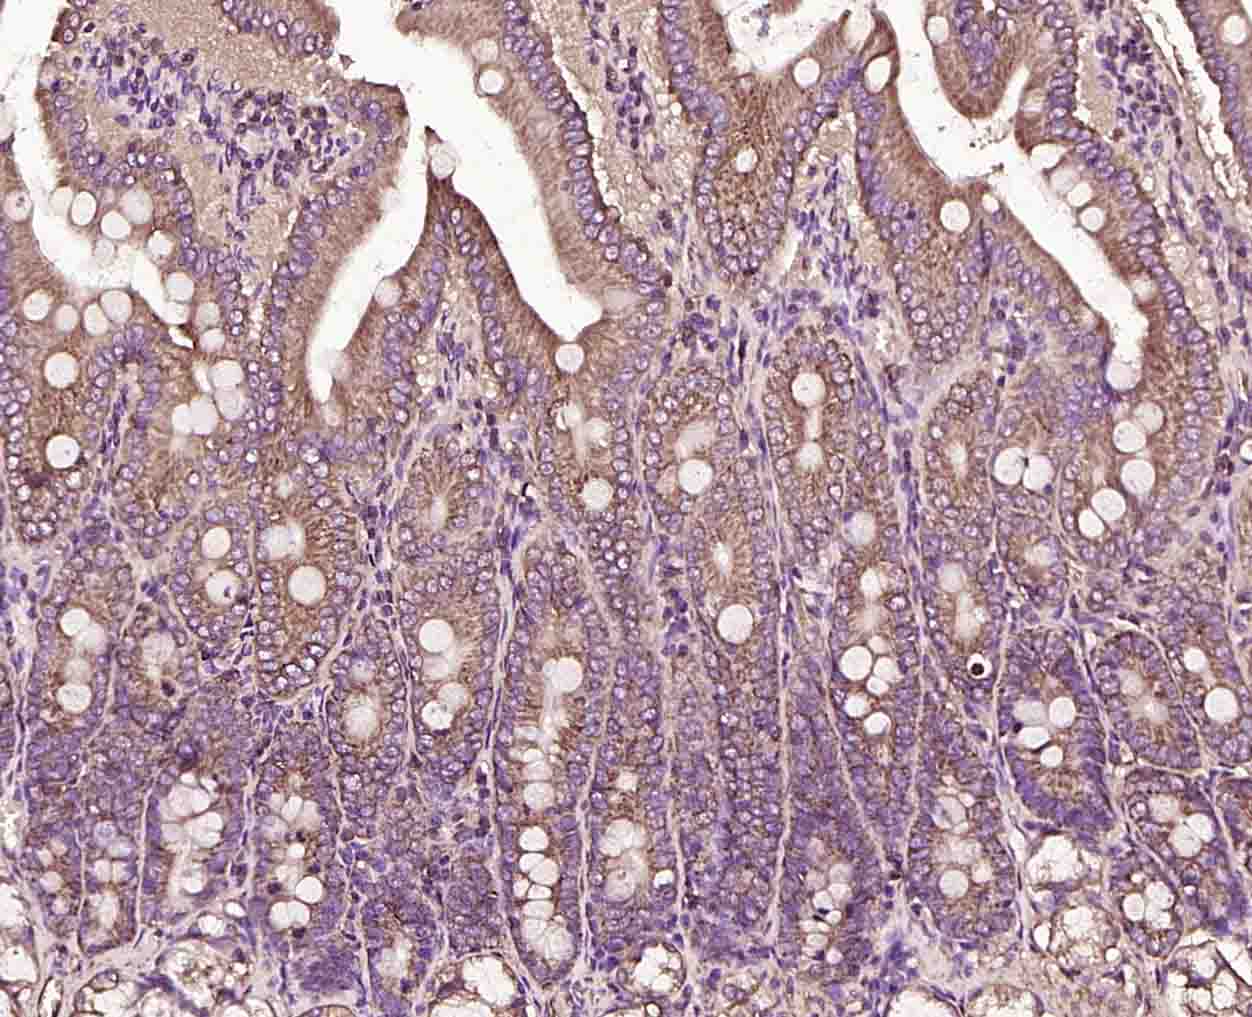

Paraformaldehyde-fixed, paraffin embedded (rat intestine); Antigen retrieval by boiling in sodium citrate buffer (pH6.0) for 15min; Block endogenous peroxidase by 3% hydrogen peroxide for 20 minutes; Blocking buffer (normal goat serum) at 37°C for 30min; Incubation with (KLK4 Rabbit pAb) Polyclonal Antibody, Unconjugated (bs-2497R) at 1:200 overnight at 4°C, followed by operating according to SP Kit(Rabbit) (sp-0023) instructionsand DAB staining.